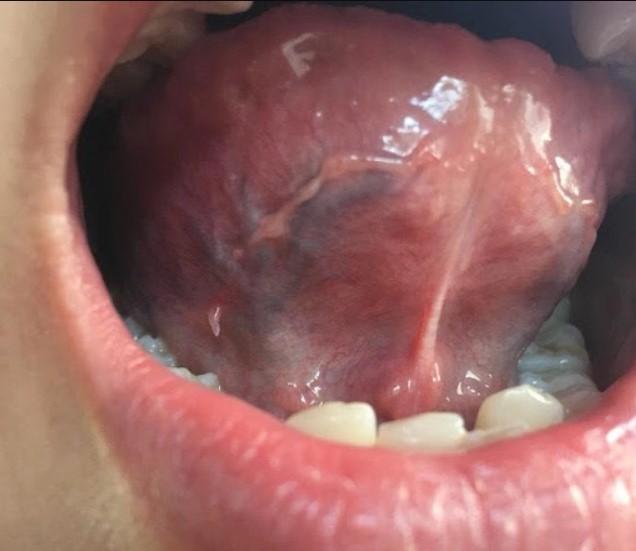

Dưới lưỡi xuất hiện sợi thịt hay thịt thừa (mụn thịt) là khi quan sát thấy lưỡi có lớp niêm mạc lồi nhỏ hoặc u nhú ở lưỡi. Các nốt mụn thịt này sẫm màu hoặc có màu da, với kích thích khoảng từ 1mm đến 2cm. Mụn thịt thường xuất hiện trên bề mặt da, nhưng đôi khi cũng xuất hiện ở các nơi nóng ẩm trong cơ thể như dưới cuống lưỡi, khoang miệng.

Một số bệnh lý là nguyên nhân làm xuất hiện các sợi thịt ở mặt dưới lưỡi, bao gồm nhóm bệnh ung thư ở khoang miệng, sùi mào gà, bị các virus gây u nhú tấn công,... Bệnh lý làm lưỡi xuất hiện sợi thịt nếu không được chẩn đoán chính xác và điều trị kịp thời có thể để lại nhiều di chứng cho cơ thể, đặc biệt là bệnh sùi mào gà và u nhú tiền đình Papillomatosis.

Mặt dưới lưỡi có sợi thịt có thể là dấu hiệu của một số bệnh lý nguy hiểm như:

Sùi mào gà có thời gian ủ bệnh khoảng 2 đến 9 tháng, rất khó đến phát hiện trong giai đoạn đầu. Mặt dưới lưỡi có sợi thịt là một dấu hiệu để nhận biết bệnh sùi mào gà, tuy nhiên bệnh thường bị nhầm lẫn với nhiệt miệng, viêm amidan hay viêm họng.

Mặt dưới lưỡi có sợi thịt sẽ không nguy hiểm nếu xác định được nguyên nhân là do u nhú tiền đình Papillomatosis. Đây là hiện tượng tăng sinh quá mức các tế bào gai ở dưới lớp biểu bì mô lưỡi.